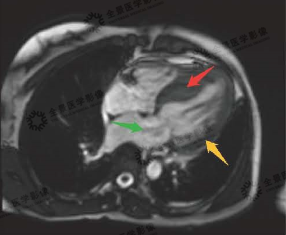

▲重度狭窄的主动脉流出道

▲电影序列

红色箭头:非对称性增厚的心肌

黄色箭头:正常心肌

绿色箭头:二尖瓣反流血流信号

▲延迟强化序列

红色箭头:部分因为损伤纤维化的心肌

磁共振显示:心肌为非对称性肥厚,且部分心肌伴有纤维化表现,该患者为非对称性肥厚型心肌病。